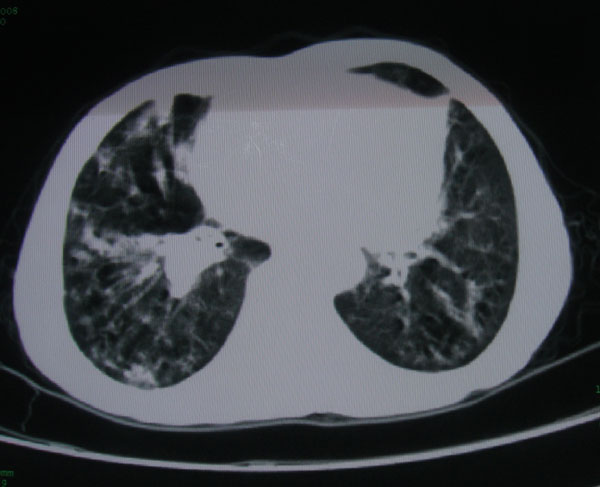

标题: CT15046:F59Y,咳嗽间断咳血丝痰就诊. [打印本页]

标题: CT15046:F59Y,咳嗽间断咳血丝痰就诊.

咳嗽\间断咳血丝痰就诊.

考虑支气管扩张并感染

1慢支伴感染;右下肺周围型肺癌。

1\\慢支并感染

2\\浸润型肺结核

本例应该是“慢性疾病并发多种合并症”即:慢支并感染并支气管扩张征!结合病灶分布 形态分析,不除外合并“继发性肺结核”!

肺间质性改变 支气管扩张合并感染

慢性支气管炎伴全小型肺气肿、支气管扩张、感染、间质纤维化。

多考虑支气管扩张并感染,双下肺继发性肺结核不除外